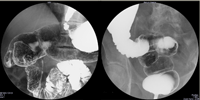

腹部の検査

オリンパスの最新鋭内視鏡システム(EVIS LUCERA ELITE)での胃内視鏡、大腸内視鏡、経鼻胃内視鏡(鼻から挿入する内視鏡)による観察(NBI観察も可能)と早期癌・ポリープ切除などの処置を行っています。また全例コンピューターでの録画を行い、検査後に録画映像にて詳細な説明を行います。さらにコンピューターファイリングシステムによる迅速な診断を行っております。